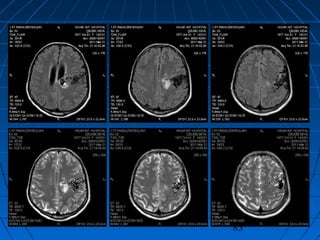

SPONTAN İNTRAPARENKİMALSPONTAN İNTRAPARENKİMAL

HEMORAJİHEMORAJİ

GENEL BİLGİLERGENEL BİLGİLER

 Nöral parenkim dokusu içineNöral parenkim dokusu içine

kanama,kanama,

 Tüm strokların % 10’uTüm strokların % 10’u

 Sıklık yılda yüzbin kişide 12 - 15Sıklık yılda yüzbin kişide 12 - 15

olguolgu

 Her yaşta görülebilir ancakHer yaşta görülebilir ancak 80 y<80 y<

25 kez fazla25 kez fazla

 Geçirilmiş bir CVAGeçirilmiş bir CVA varsa risk çokvarsa risk çok

SPONTAN İNTRAPARENKİMAL HEMORAJİSPONTAN İNTRAPARENKİMAL HEMORAJİ

ETYOLOJİETYOLOJİ

 HipertansiyonHipertansiyon

 Serebral kan akımınınSerebral kan akımının

ani artışıani artışı

 Vasküler anomalilerVasküler anomaliler

 ArteriopatilerArteriopatiler

 TümörlerTümörler

 Kanama diyateziKanama diyatezi

 EnfeksiyonEnfeksiyon

 Dural venöz trombozDural venöz tromboz

 İlaç kullanımıİlaç kullanımı

 EklampsiEklampsi

PATOLOJİPATOLOJİ

 Lentikülostriat, talamoperforanLentikülostriat, talamoperforan

ve baziler arter paramedianve baziler arter paramedian

dallarındakidallarındaki Charcot - BouchardCharcot - Bouchard

anevrizmalarıanevrizmaları

 Amiloid anjiopatiAmiloid anjiopati

 Hemorajik tümörlerHemorajik tümörler

KLİNİKKLİNİK

 Ani başlangıçAni başlangıç

 Bilinç yitimi - nörolojikBilinç yitimi - nörolojik

defisitdefisit

 KusmaKusma

 KİBASKİBAS semptomlarısemptomları

 Yerleşim yerleri :Yerleşim yerleri :

• Bazal ganglionlarBazal ganglionlar

% 37% 37

• TemporalTemporal %%

2020